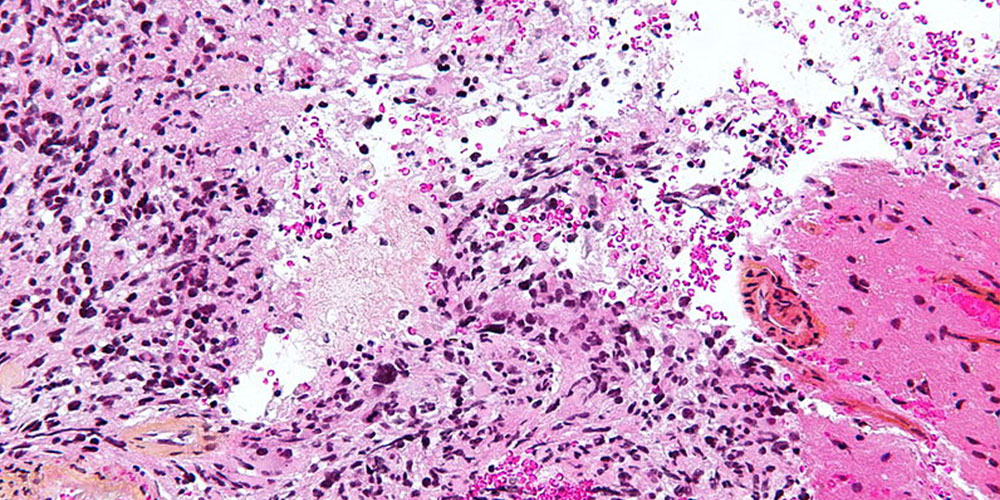

Микрофотографии гистологии глиобластомы головного мозга